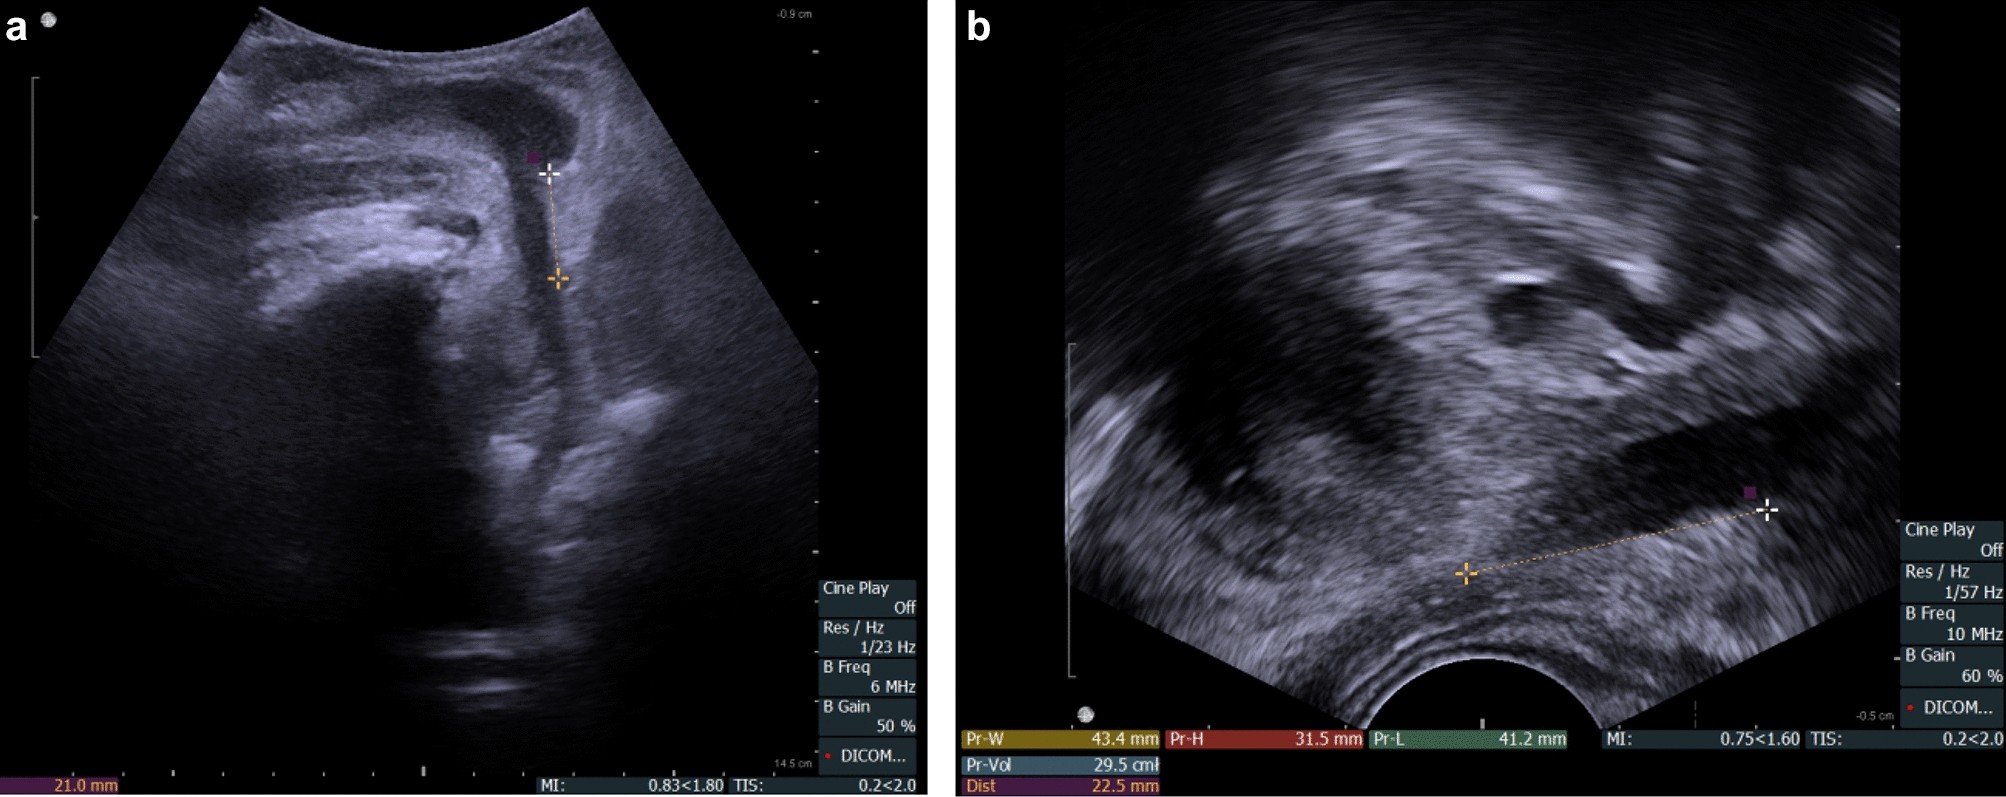

Transperineal Ultrasound As A Reliable Tool In The Assessment Of Membranous Urethra Length In Radical Prostatectomy Patients Scientific Reports